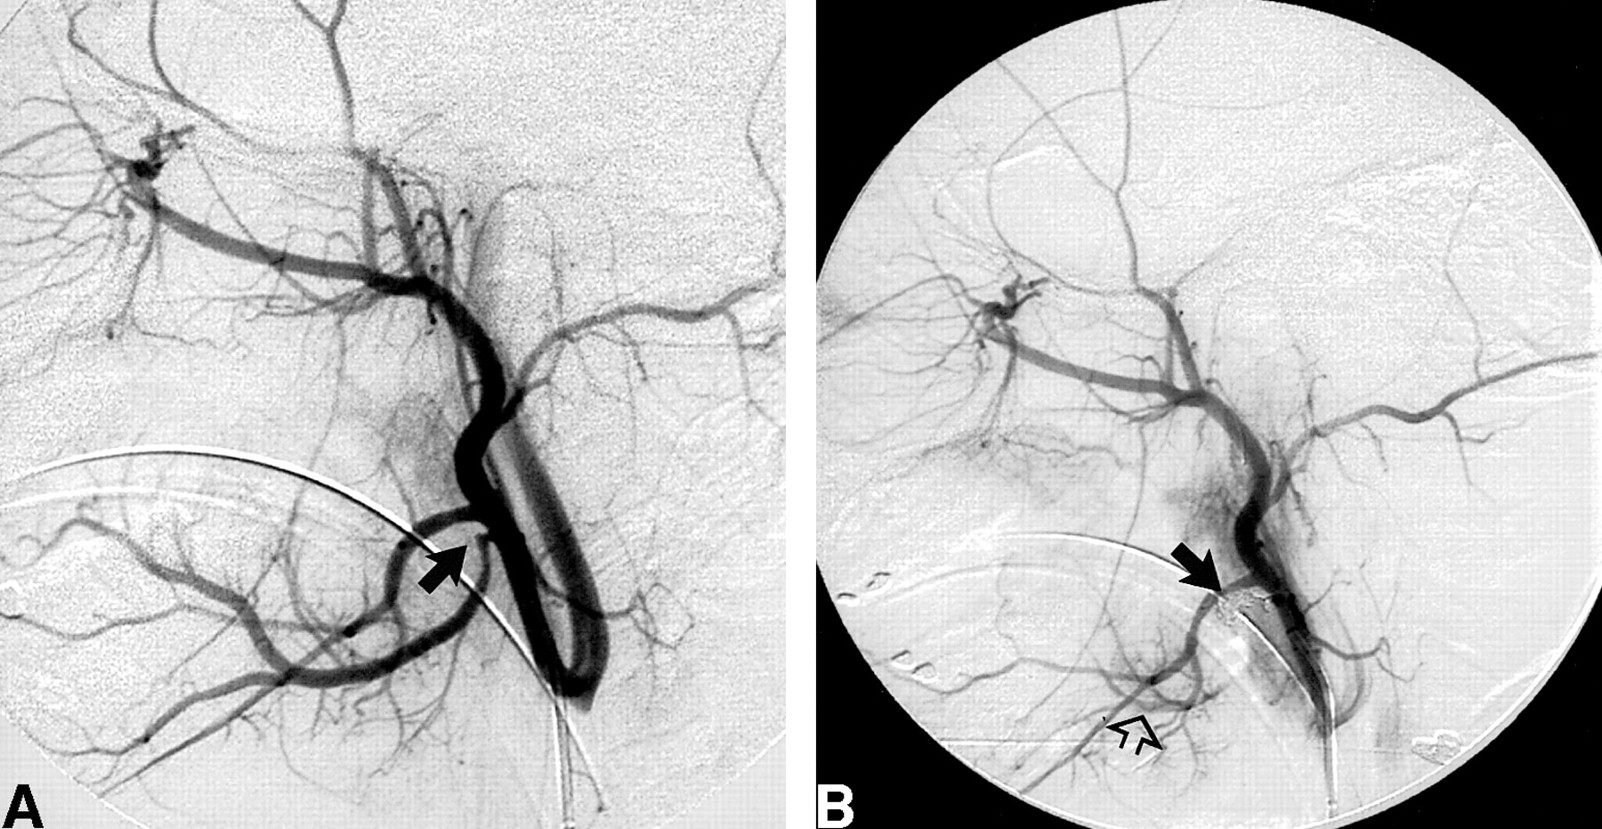

Case 1: 10-year-old girl with PTAH.

A, Right common carotid artery angiogram shows elongation and abrupt truncation of the ascending palatine artery (arrow). This finding was considered suspicious in light of recent PTAH.

B, An ECA angiogram reveals coil embolization of the distal ascending palatine artery (solid arrow). Mild catheter-induced spasm is noted along the main ECA trunk (open arrow) that is not apparent in A.

Under general anesthesia, the right common femoral artery was punctured, and a 5F sheath was inserted. A 5F catheter was used to select the right common carotid artery, right external carotid artery (ECA), right ascending pharyngeal artery, and left common carotid artery. Biplane arteriography of the head was performed. The right internal carotid artery (ICA) was intact, although deviated in its course, presumably as a result of a hematoma within the adjacent soft tissues. No active extravasation was encountered, although the right ascending palatine artery had a suspicious appearance with an elongated and truncated configuration thought to correspond in location to the junction area of the tonsillar bed and soft palate (Fig 1A). In the absence of active extravasation of contrast material, the precise site of arterial injury was difficult to confirm; however, the appearance of the ascending palatine artery on the right was sufficiently suspicious to warrant intervention, particularly given recent clinical events. After coaxial selection with a TurboTracker 18 microcatheter (Target Therapeutics, Fremont, CA), three 10-mm fiber coils (Target Therapeutics) were placed consecutively along the distal course of the right ascending palatine artery, resulting in a satisfactory angiographic appearance of distal occlusion of that vessel (Fig 1B). No other embolization was performed in the absence of identifiable arterial abnormalities. The patient tolerated the procedure well, recovered without incident, and was discharged on the fourth hospital day. Subsequent evaluation after our intervention confirmed the presence of type I von Willebrand disease.